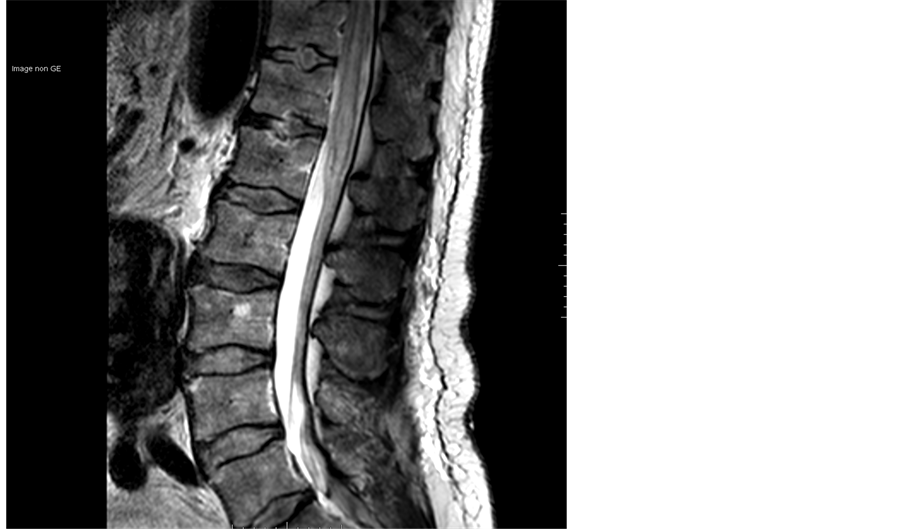

The immediate postoperative recovery was uneventful. Forty-four hours later he began to regain a little sensory and motor function to his legs. When another MRI was performed, this revealed spinal cord ischemia from the level of T10 to terminus cone (Figure 4).

Figure 4. Post-operative lumbar MRI: apparition of a large T2 hypersignal confirming the Cauda equina syndrome.